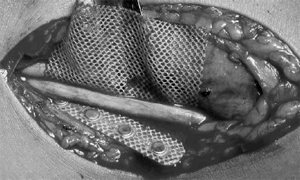

Fig. 3 Mesh around the nerve to secure the electrode and prevent

migration.